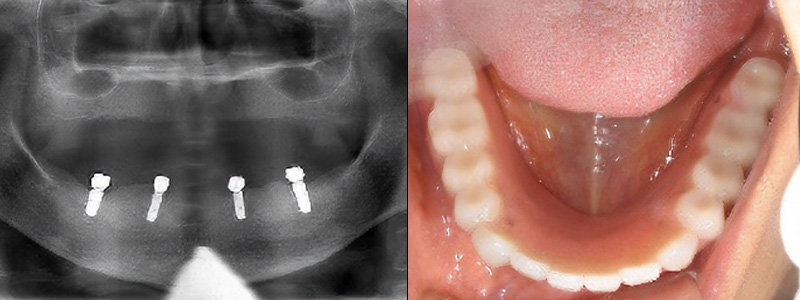

- 治療名

- インプラントオーバーデンチャー

- 治療内容

- 下顎にインプラント・入れ歯治療

- 患者様

- 70代女性

- 治療期間

- 9ヶ月

- 費用

- ¥2,035,000

- 治療に対するリスク

- 外科処置に対する疼痛合併症のリスク

- 執刀医

- Dr.村尾